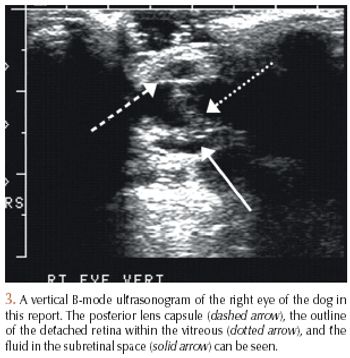

A 12-year-old 57-lb (26-kg) castrated male Siberian husky was presented to the Colorado State University Veterinary Teaching Hospital for evaluation of blindness of three weeks' duration, depression, and polydipsia.